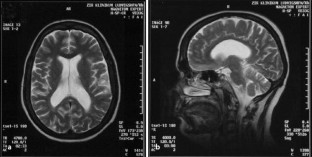

Abb. 3